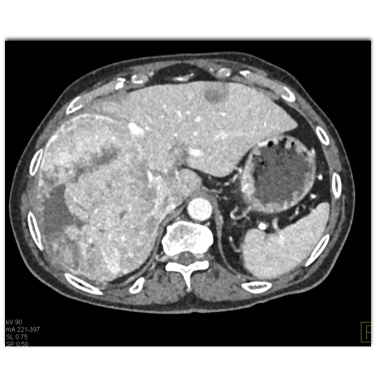

The most likely diagnosis in this case is?

hepatoma

hepatic adenoma

MCN (mucinous cystic neoplasm)

hemangioma